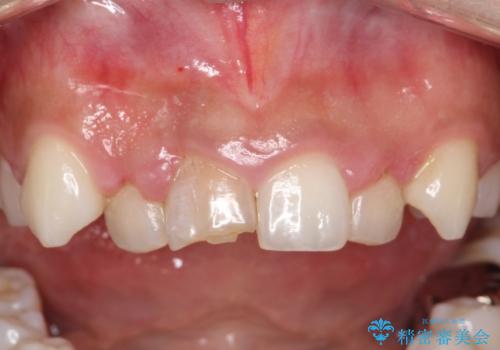

- セラミック矯正希望で来院された患者さんです。

歯周組織の状態が悪く、この状態ではきれいにかぶせものを入れることができないため、仮歯にかえてある程度見た目を改善した上で、歯周基本治療を進めることに。

歯肉の状態が改善できたら、セラミックに変えていく治療計画を立てました。